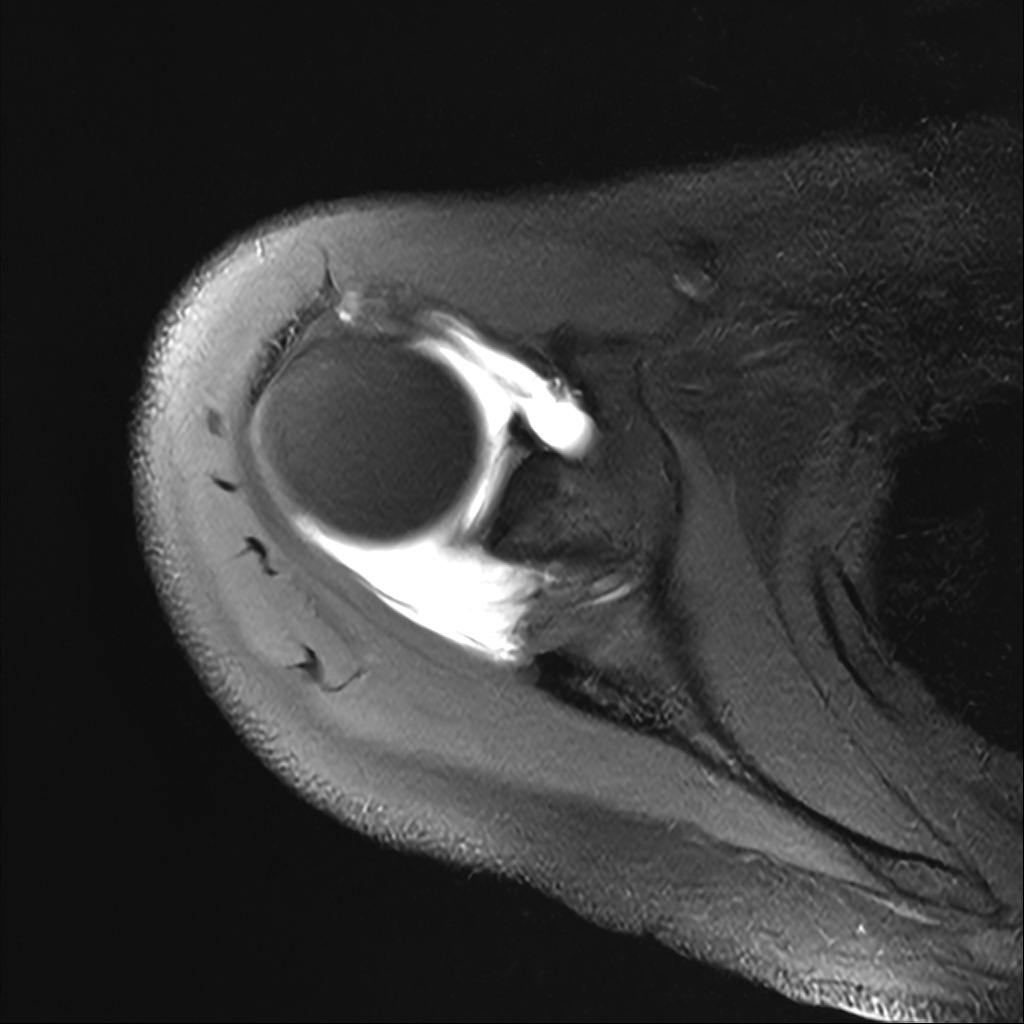

Mri 단면 영상으로 보아 어깨 관절 부위에서 이상 신호가 관찰되고 이는 관절 와순 파열의 가능성을 시사할 수 있습니다.

하지만 이영상만으로 정확한 진단은 불가능하고 정밀한 판단을 위해선 전체 시퀀스와 영상의학과 전문의의 공식판독이 필요합니다 특히 와순 파열은 위치와 동반 병변에 따라 해석이 달라집니다!